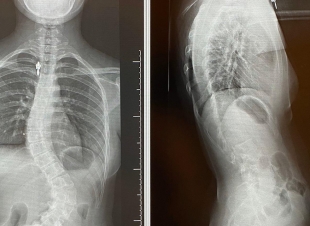

إنهاء معاناة مريضين من إنحناء للعمود الفقري في بيشة